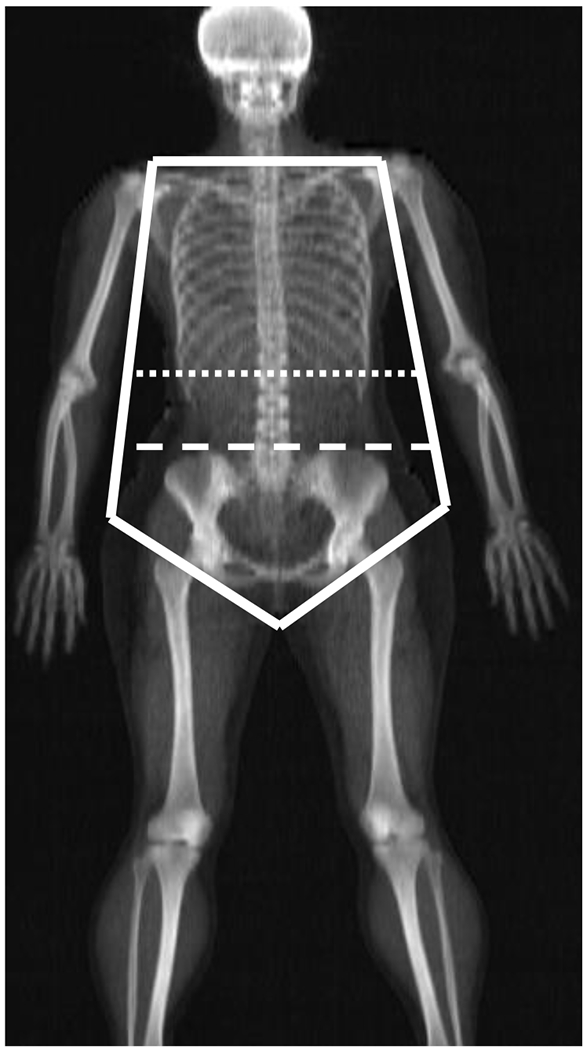

Impact of the Seated Height to Stature Ratio on Torso Segment Parameters

Ergonomic modelling programmes such as the Three Dimensional Static Strength Prediction Programme (3DSSPP) are valuable tools for assessing strength capabilities and risk assessment. These tools rely on accurate, representative inputs in the form of body segment parameters (BSPs). The upcoming version of 3DSSPP will employ BSPs for the torso, split into thoracic, lumbar and pelvis segments in order to more precisely determine spinal forces and injury risks. This study determines the impacts of age, body mass index and the estimated seated height to stature ratio (SHS) on these full and split torso parameters in a sample of working American adults. The results show that all of these metrics have significant relationships with the BSPs of interest, indicating that they must be accounted for when determining these parameters. A sensitivity analysis performed in 3DSSPP demonstrates that varying the parameters inputs will have large effects on L5/S1 compression force calculations. | Current anthropometric data sets for ergonomic applications do not account for wide ranges of age, BMI and overall body shape on segment parameter calculations. This study quantifies the associations of age, BMI and the seated height to stature ratio on full and split torso segment parameters. | 3DSSPP: Three-Dimensional Static Strength Prediction Program; BMI: body mass index; BSP: body segment parameter; BW: body weight; COM: centre of mass; DXA: dual energy x-ray absorptiometry; R|: radius of gyration; SHS: seated height to stature ratio; SL: segment length.